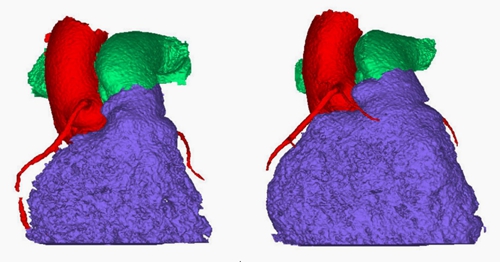

手術(shù)的關(guān)鍵和難點(diǎn)在于要對(duì)右心室流出道進(jìn)行精確評(píng)估,精準(zhǔn)定位肺動(dòng)脈瓣膜植入位置,并將瓣膜準(zhǔn)確無誤植入最佳評(píng)估位置。鑒于法洛四聯(lián)癥矯治術(shù)后右心室流出道解剖結(jié)構(gòu)的復(fù)雜性,為最大程度提高瓣膜匹配度,團(tuán)隊(duì)通過交互式醫(yī)學(xué)影像控制系統(tǒng)對(duì)右心室流出道進(jìn)行重建,精密測(cè)量多個(gè)部位尺寸,確定了最佳的肺動(dòng)脈瓣膜型號(hào)和植入位置。

術(shù)前三維CT掃描測(cè)量肺動(dòng)脈及右室流出道各個(gè)位置的尺寸大小

術(shù)前三維CT掃描數(shù)據(jù)分析肺動(dòng)脈瓣區(qū)域預(yù)先擴(kuò)張對(duì)于冠脈的解剖位置關(guān)系